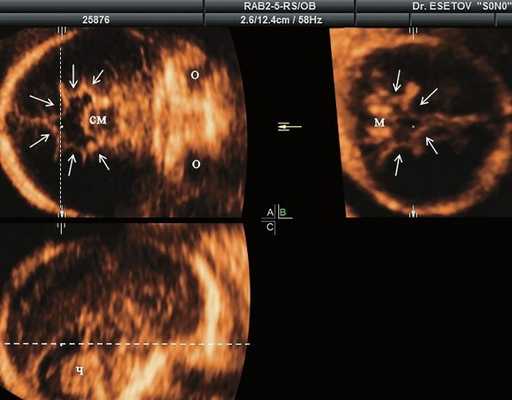

а) Ультразвуковая трехмерная реконструкция (СМ - средний мозг, О - орбита, Ч - червь, М - мозжечок). На плане А показан нижнеаксиальный срез на уровне среднего мозга и орбит, показывающий аномальную бороздчатость медиальной поверхности височных долей (стрелки). Уровень получения этого среза отражен пунктирной линией на плане С. На плане B показан коронарный мозжечковый срез, на котором также отражены выпуклые извилины медиальной поверхности височных долей (стрелки). Пунктирная линия на плане А показывает уровень получения коронарного среза.

Во всех представленных наблюдениях проводилось целенаправленное исследование структур мозга плодов для оценки наличия признаков ДВД. Согласно данным литературы, использовались низкие аксиальные и коронарные трансмозжечковые срезы.

В наблюдениях 1-3 наличие изогнутой бедренной кости (по типу "телефонной трубки") (рис. 1в, 2г, 3г) позволяло предположить наличие ТД I типа. Целе направ ленное исследование головного мозга этих плодов в дополнение к описанным скелетным признакам показало и картину ДВД. Была выявлена аномально повышенная бороздчатость и выпуклость извилин нижнемедиальной поверхности височных долей у плодов в наблюдениях 1-3 (рис. 1а, 2б, 3б). Это позволило установить диагноз ТД I типа.

В таких случаях провести дифференциальную диагностику и установить диагноз ТД I типа позволяет обнаружение у плодов при эхографии признаков ДВД, что было показано в представленных наблюдениях 1-3.

В последнее десятилетие были представлены исследования, показавшие возможность выявления ультразвуковых признаков ДВД у плодов с ТД, начиная с 19-20 нед, как проспективно, так и ретроспективно 9. Было показано, что оптимальными срезами для пренатальной диагностики признаков ДВД являются низкий аксиальный срез, включающий средний мозг и орбиты, и коронарный трансмозжечковый срез.

Результативность этих срезов обусловлена тем, что аномальная бороздчатость при ТД бывает выражена, главным образом, в нижних отделах височных долей. Этим же обусловлено то, что эти признаки остаются не диагностированными при стандартных аксиальных скрининговых срезах оценки структур головного мозга плода, которые проходят выше области поражения височной доли при ТД.